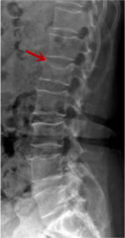

利器一:X線/DR

腰椎X線片作為最基礎(chǔ)的影像檢查手段,利于X線穿透人體組織后成像,以其快捷、直觀、價格低廉的特點,X線檢查主要包括腰椎正側(cè)位、雙斜位以及過伸過屈位。主要用于觀察腰椎骨骼的情況,如椎體是否有骨折、骨質(zhì)增生程度、生理曲度的變化、椎體移位的情況等。然而,X線檢查也有它的局限性,無法判斷是骨折的新舊,對于椎體內(nèi)部結(jié)構(gòu)和周圍肌肉韌帶組織(如脊髓神經(jīng)、椎間盤、韌帶等)的顯示不佳,另外X線作為有輻射檢查,孕婦及嬰幼兒謹慎選擇。

箭頭提示腰3椎體滑脫